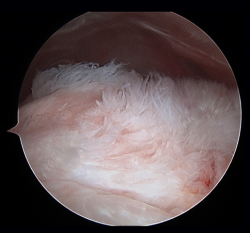

Figure 1. Arthroscopic view from the posterior portal in a case of severe supraspinatus tendinosis of a left shoulder.

Traditionally, the appearance of rotator cuff disease has been described as a progressive disorder that initially manifests as acute tendinitis, continues as tendinosis with tissue degeneration and partial ruptures, and ultimately results in full thickness rupture(6). The terms tendinitis and tendinosis represent different stages of tendinopathy. Tendinitis refers to acute or chronic pain associated by definition to inflammation, even if the histological studies show an absence or only minimal presence of inflammatory cells(7). Tendinosis in turn refers to degenerative disease with or without inflammation (Figure 1). Tendinopathy is the term used to describe a clinical condition characterized by pain and functional alteration of the tendons of the rotator cuff, without specification of the concrete causal mechanism involved(8).